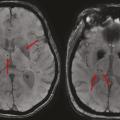

Microbleeds, en hausse avec l’âge

Les microbleeds sont des effractions de sang dans le parenchyme cérébral. À l’IRM, ce sont de petites lésions rondes de 2 à 5 mm, homogènes et très hypo-­intenses en séquence de susceptibilité magnétique comme la séquence T2 écho de gradient (T2*) [fig. 3]. Ils ne sont pas visibles au scanner. Dans la maladie des petites artères cérébrales, ils sont typiquement localisés dans les territoires profonds du cerveau (ganglions de la base, tronc cérébral et cervelet).5

Leur prévalence augmente avec l’âge. Ils sont associés à un risque hémorragique mais également ischémique.

Ils sont à différencier des microbleeds lobaires périphériques, plutôt évoqués lors d’une angiopathie amyloïde cérébrale non liée à l’hypertension artérielle.